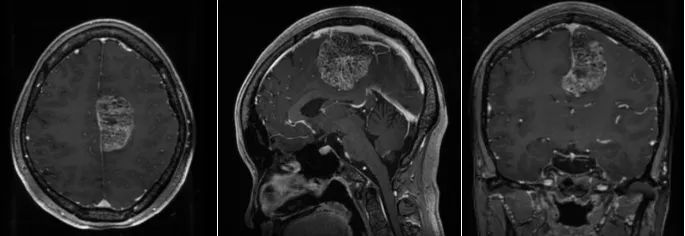

随即,张女士一家前往上海市静安区中心医院(华山医院静安分院)就诊。经头颅MRI检查显示,脑肿瘤位于左侧大脑额顶叶功能区,且血供异常丰富,切除难度高,手术风险巨大。

面对这一棘手情况,华山医院鲍伟民教授和顾昕主任团队开展了严谨的术前讨论评估。顾昕认为,该患者左额顶功能区巨大脑膜瘤,手术指征非常明确。考虑到脑膜瘤体积大,血供丰富,术中极易出现大出血,同时切除肿瘤时,易损伤周边重要动静脉,造成不可逆的大面积脑梗死及回流障碍,术后出现肢体偏瘫麻木,脑肿胀脑出血甚至昏迷死亡。讨论后,建议采取导航下精准定位,保护好中央沟静脉及中央前后回,分块切除肿瘤。